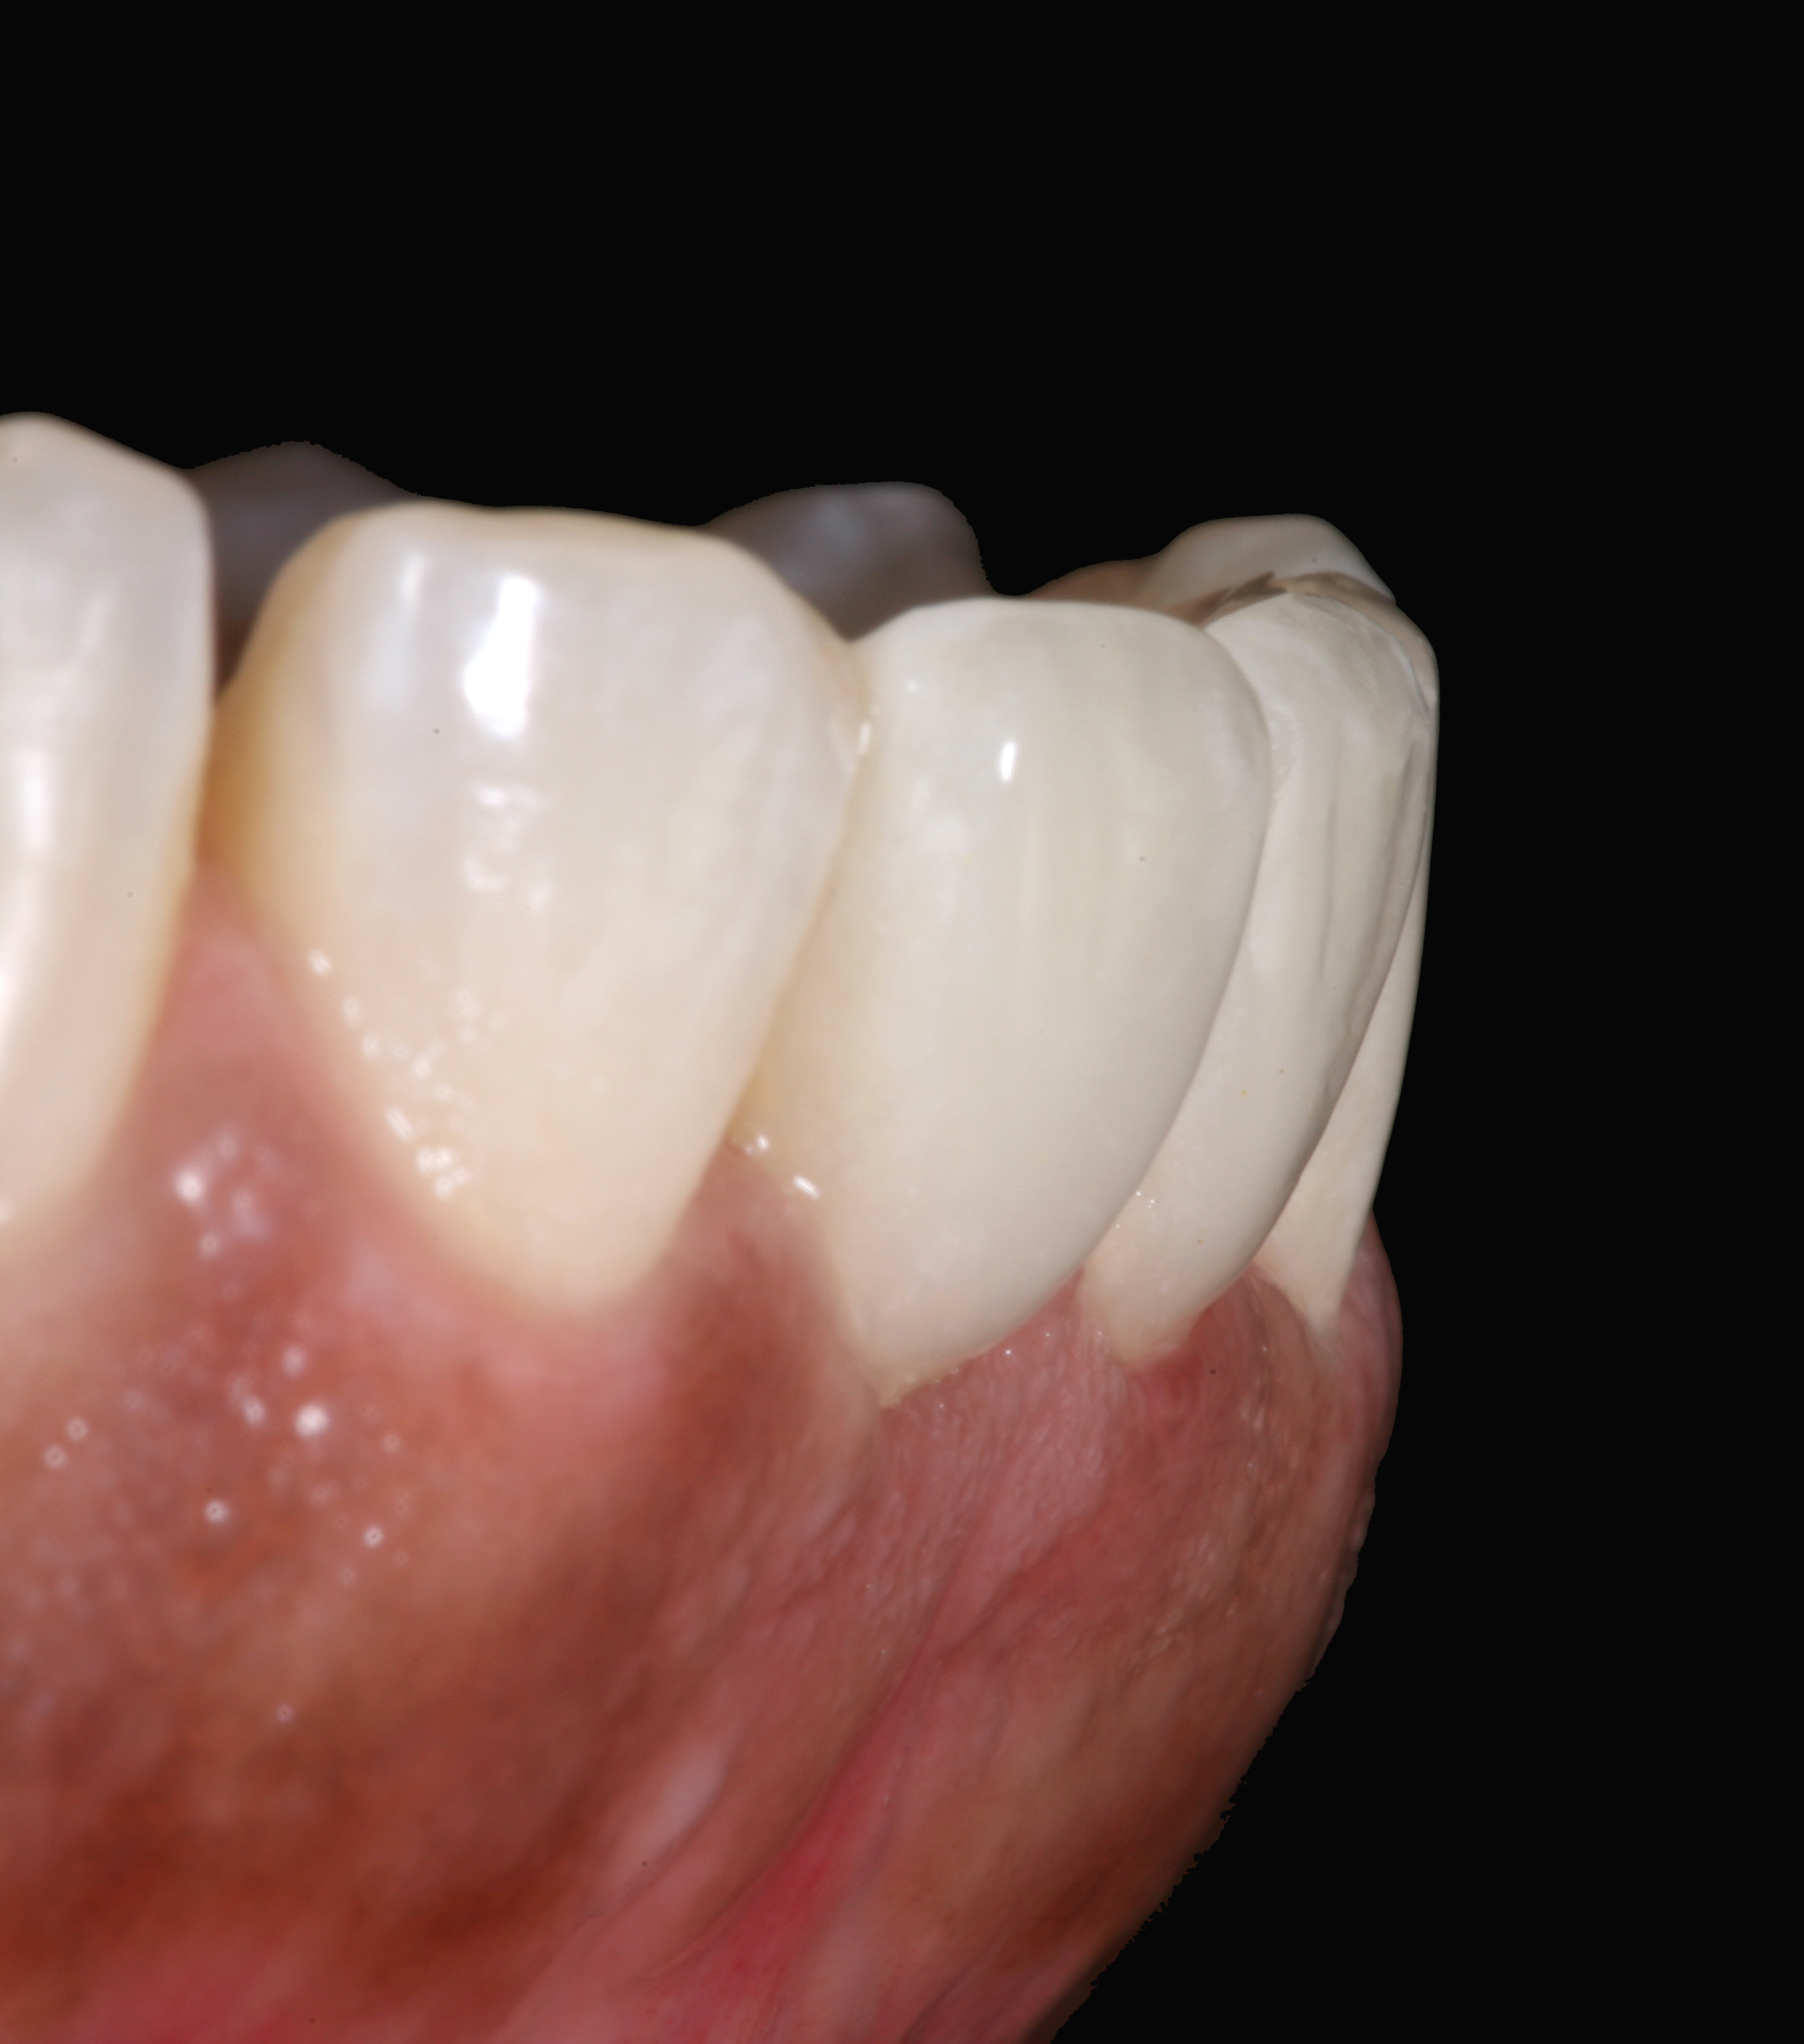

Postoperative situation: left lateral view.

Figure 11

Postoperative situation: right lateral view.

Figure 12